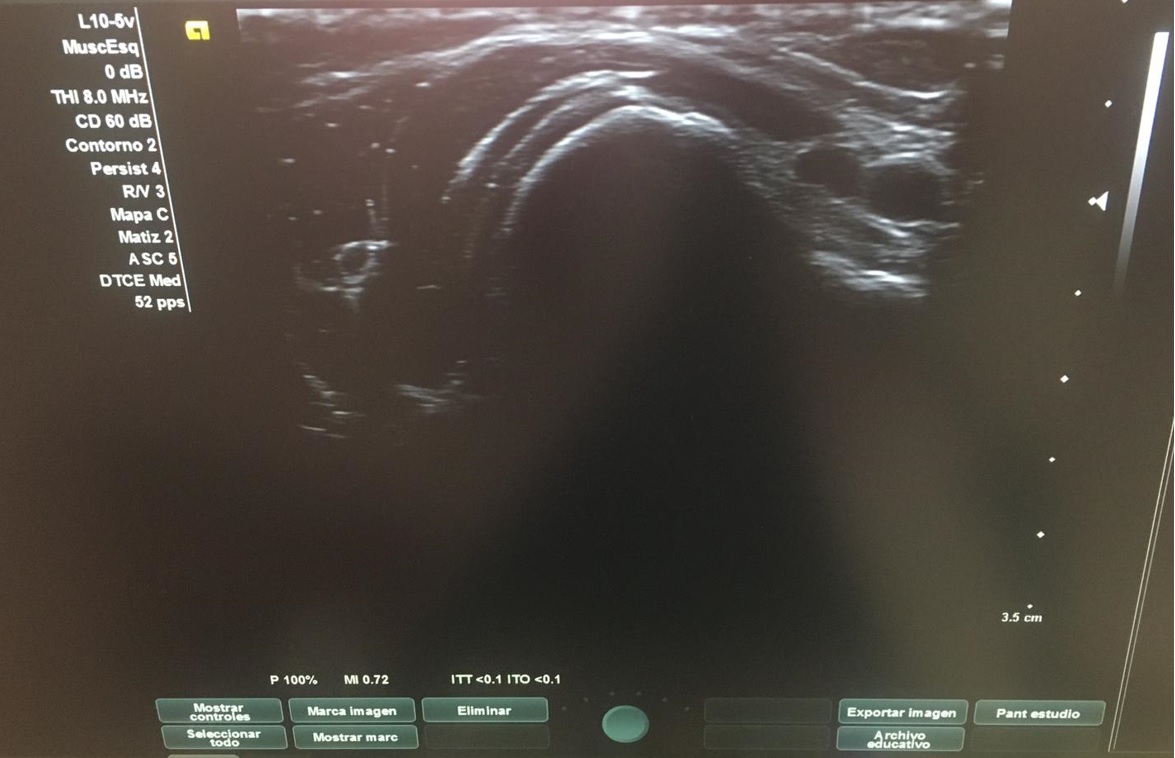

Con el objetivo de no irradiar al escolar, se decide realizar una ecografía desde el centro de salud, para poder obtener una mayor aproximación diagnóstica.

Ecografía: La tumoración referida corresponde a una excrecencia ósea con ribete hipoecoico circunante de 1 mm de espesor, sugestiva de lesión osteocondral.

Tras visualizar alteración en la ecografía del centro de salud, se deriva a radiología para realizar ecografía reglada y completar estudio con radiografía, así como realizar derivación para valoración por parte de Traumatología del Hospital Santa Lucía.

Gracias a la ecografía de Atención Primaria, se ha podido llegar al diagnóstico de manera precoz así como acortar los tiempos de espera.